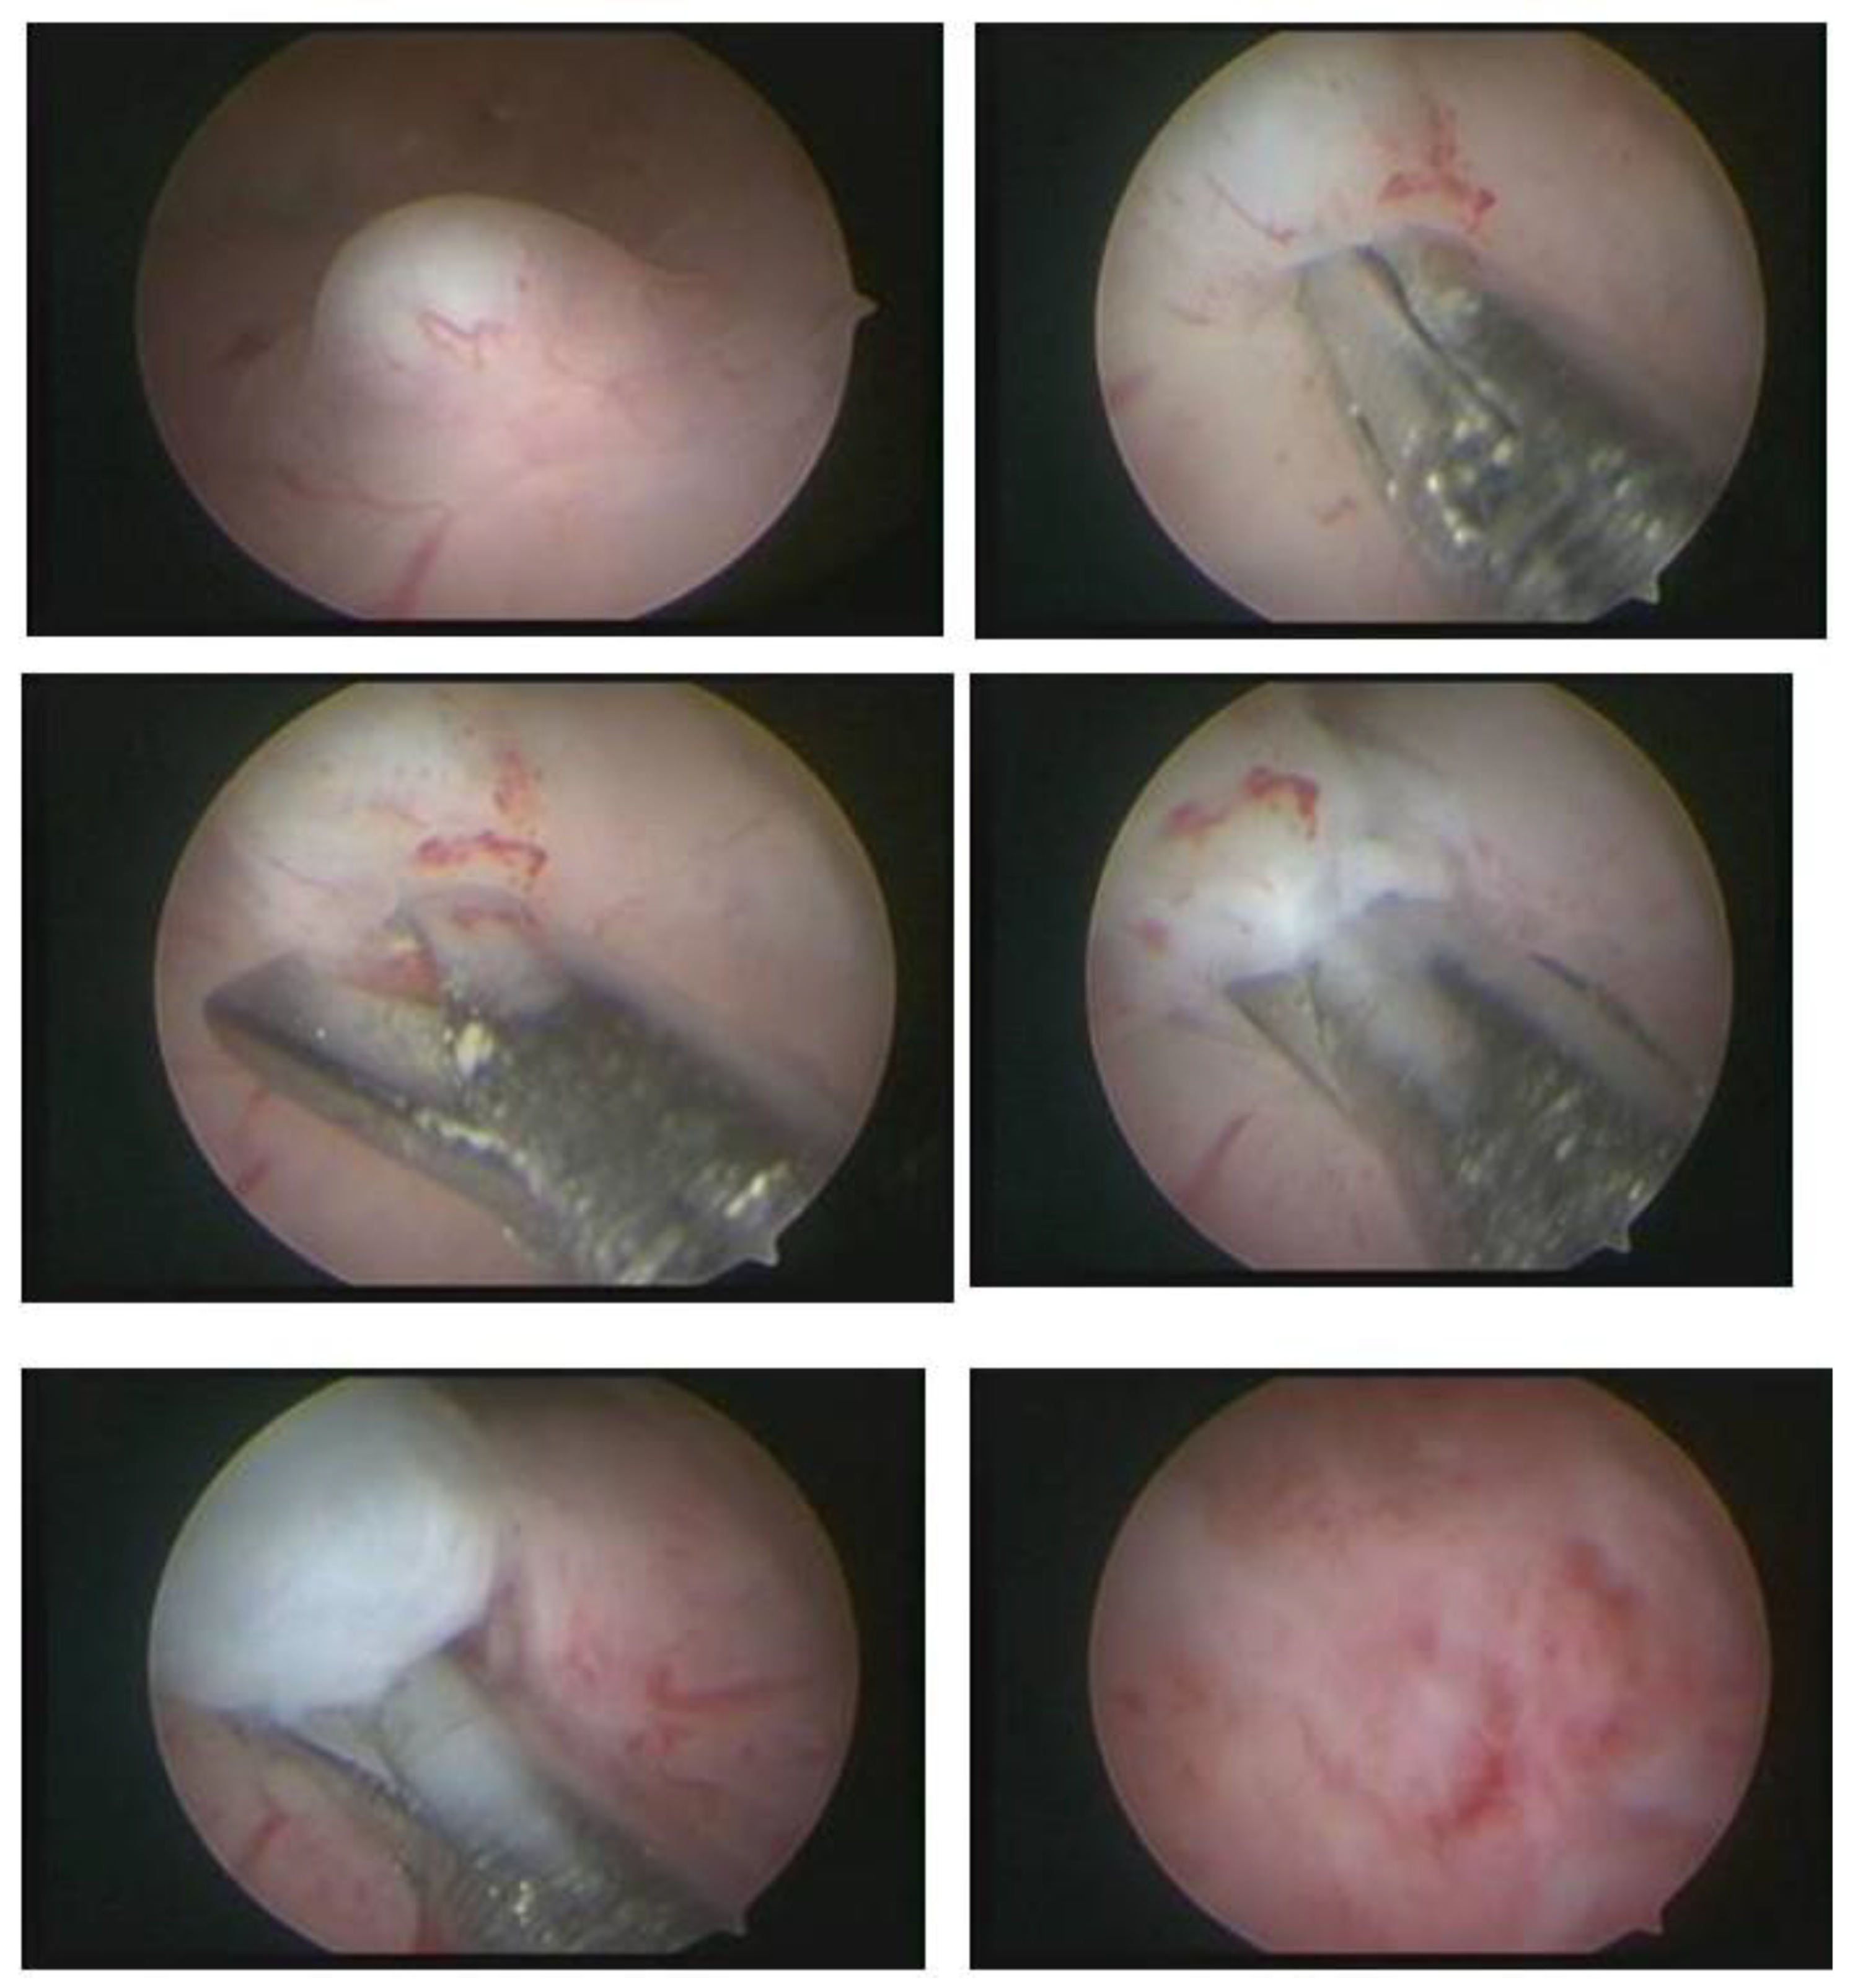

The technique with the resectoscope, regardless of the type of energy, is the same, with planned loop movements always in the fundus–cervical direction, with the angulation of the resectoscope axis to define the degree of resection depth. These two movements have to be thought out and prepared before activating the energy so that only the myoma is resected, avoiding resection of the myometrium and the risk of perforation, and so that the penetration of the cut is as desired, without risk (Figure 9).

Figure 9. Correlation with hysteroscope angulation and tissue depth.